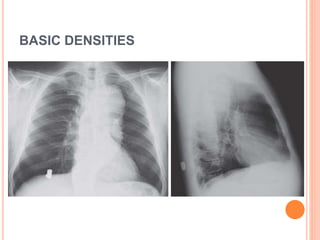

THE FIVE BASIC DENSITIES

BASIC DENSITIES